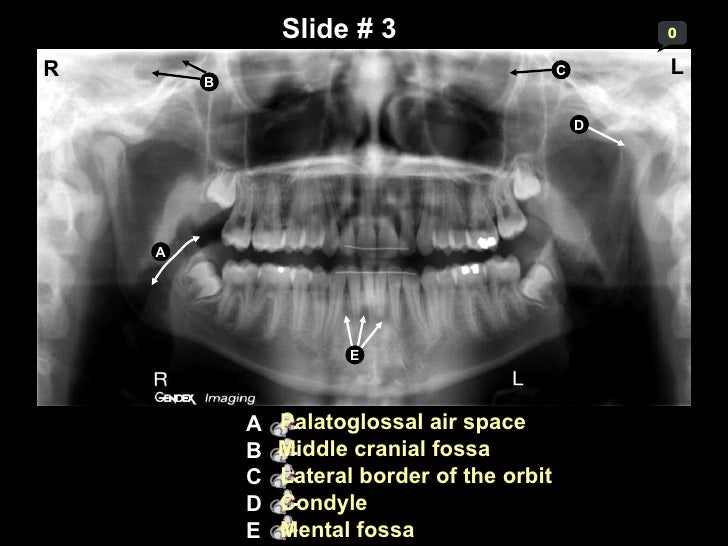

Self Study-pan-anatomy

Self study-pan-anatomy www.slideshare.net

palatoglossal fissure pterygomaxillary foramen mandibular pterygoid palate